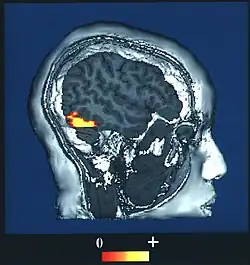

Computer-enhanced fMRI scan of a person who has been asked to look at faces. The image shows increased blood flow in cerebral cortex that recognizes faces (FFA). | |

The FFA was discovered and continues to be investigated in humans using positron emission tomography (PET) and functional magnetic resonance imaging (fMRI) studies. Usually, a participant views images of faces, objects, places, bodies, scrambled faces, scrambled objects, scrambled places, and scrambled bodies. This is called a functional localizer. Comparing the neural response between faces and scrambled faces will reveal areas that are face-responsive, while comparing cortical activation between faces and objects will reveal areas that are face-selective.

Another study found that there is stronger activity in the FFA when a person sees a familiar face as opposed to an unfamiliar one. Participants were shown different pictures of faces that either had the same identity, familiar, or faces with separate identities, or unfamiliar. It found that participants were more accurate at matching familiar faces than unfamiliar ones. Using an fMRI, they also found that the participants that were more accurate in identifying familiar faces had more activity in their right fusiform face area and participants that were poor at matching had less activity in their right fusiform area.[20]